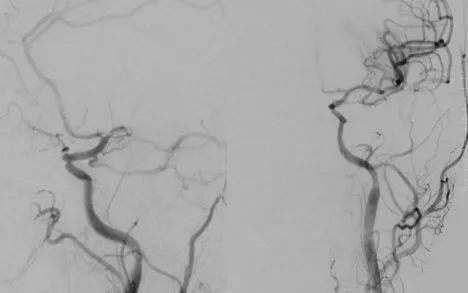

VTV.vn - Số ca đột quỵ não nhập viện trong tình trạng nặng đang gia tăng, đáng lo ngại khi ngày càng nhiều bệnh nhân ở độ tuổi trung niên và người trẻ.

Thời gian gần đây, Khoa Cấp cứu - Bệnh viện Đa khoa Quốc Oai (Hà Nội) liên tục tiếp nhận nhiều trường hợp đột quỵ não với diễn biến nặng. Đáng chú ý, tỷ lệ người bệnh ở độ tuổi trung niên và người trẻ có xu hướng tăng rõ rệt, phản ánh tình trạng trẻ hóa của căn bệnh nguy hiểm này.